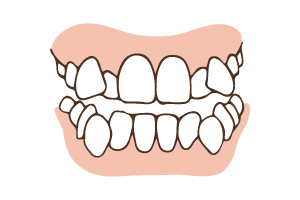

「うちの子は歯並びがキレイ」と思っていても、実は良くない歯並び(=不正咬合)が子ども達の身体に影響を及ぼしているという例が増えています。

特に気付きにくいのが「ディープバイト」。

特に気付きにくいのが「ディープバイト」。

上下の噛み合わせが深く、下の前歯が隠れるような状態です。お口の中の容積が狭くなり、下の位置が確保しにくくなり、歯ぎしりやいびきなどの症状に繋がる可能性があります。

歯並びは、横方向に歯がきれいに並ぶだけでなく、かみ合わせの高さも大切です。